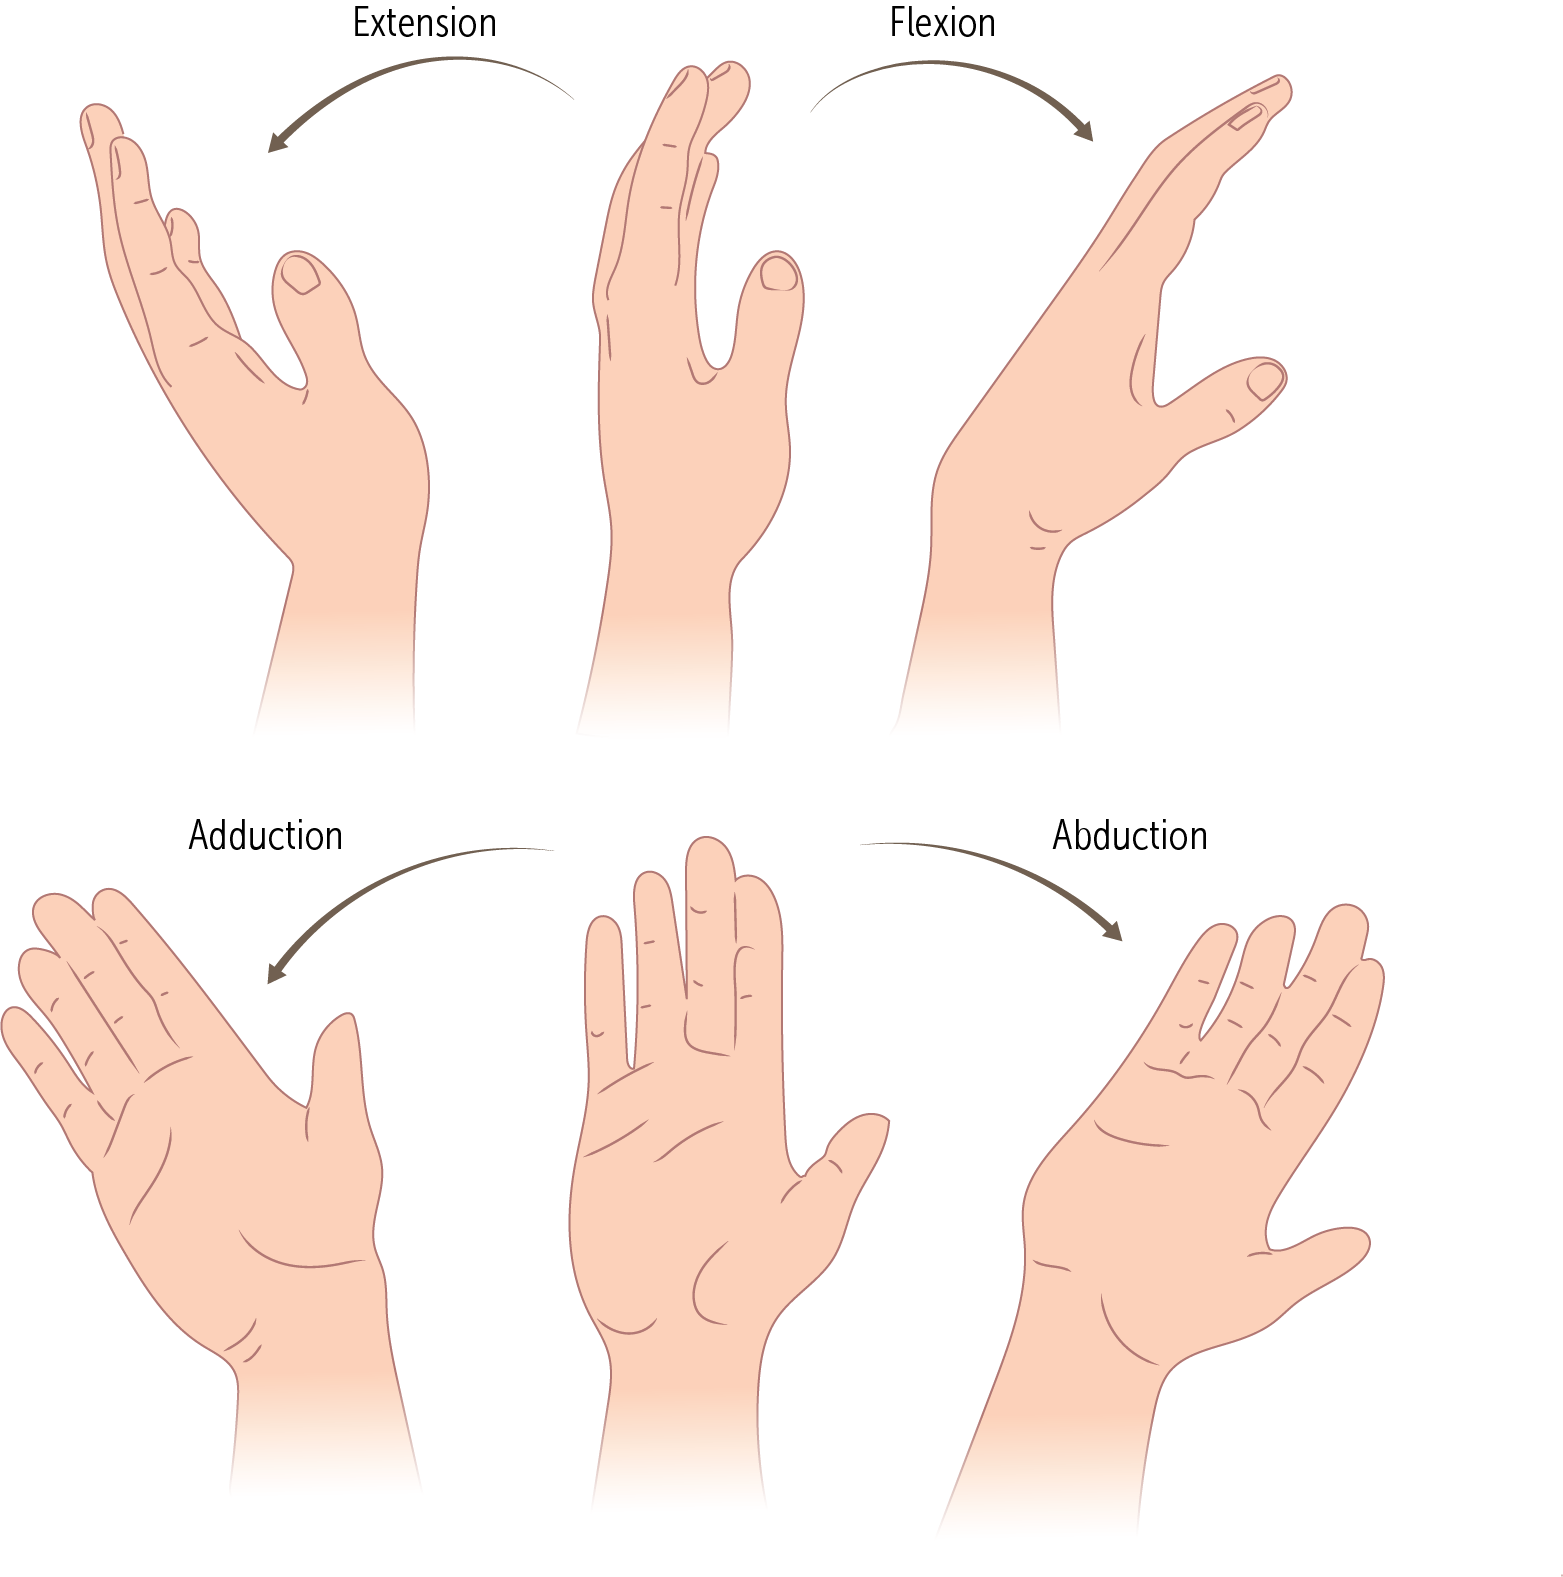

The wrist’s main action is simple ________and _________, it also moves in the plane of the palm, during _________ and _________.

flexion, extension, abduction, adduction

_________and _________are also known as radial deviation and ulnar deviation, respectively

Abduction, adduction